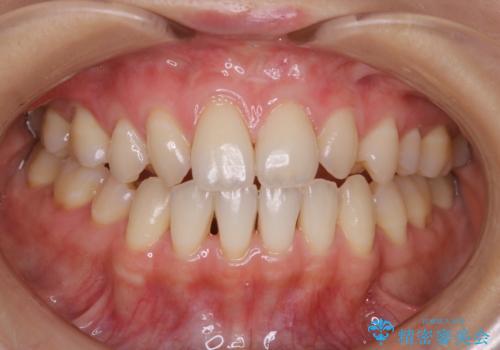

大好きなブラックコーヒーによる歯の着色を綺麗にしたい